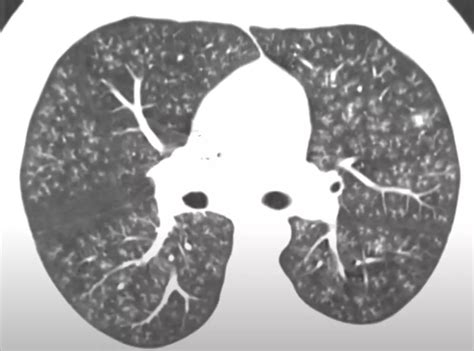

Diagnosing popcorn lung involves a combination of medical history, physical examination, and diagnostic tests. Doctors may use the following methods to diagnose the condition:

• Chest X-ray or CT scan

These tests can help doctors determine the extent of lung damage and rule out other potential causes of symptoms. A Popcorn Lung Picture from a CT scan or X-ray can provide visual evidence of the inflammation and scarring in the lungs.